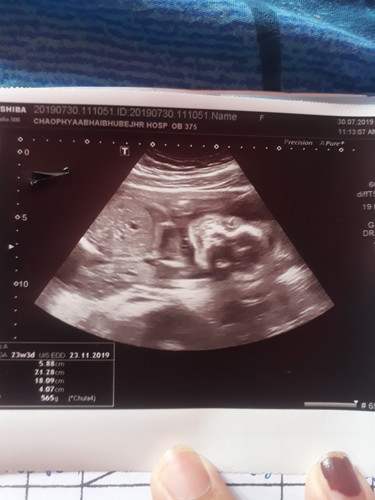

ในใบซาวด์อายุครรภ์23w นับประจำเดือน28w จะนับอายุครรภ์ตามไหนคะ

ตามใบซาวด์นะคะคุณแม่ คุณหมอจะประเมินอายุครรภ์จาก นน หรือ ขนาดน้อง ตอนซาวด์ค่ะ แม่นยำกว่านับประจำเดือนค่ะ เพราะบางทีช่วงนั้นเราอาจจะไข่ตกช้าได้ค่ะ